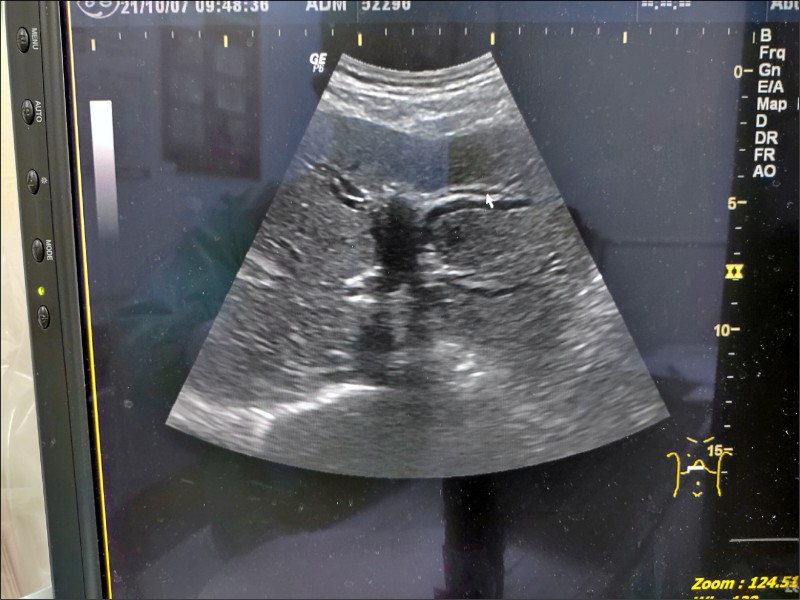

內視鏡超音波揪出胰臟癌膽管12指腸造口術解黃疸 銀髮天地 自由健康網